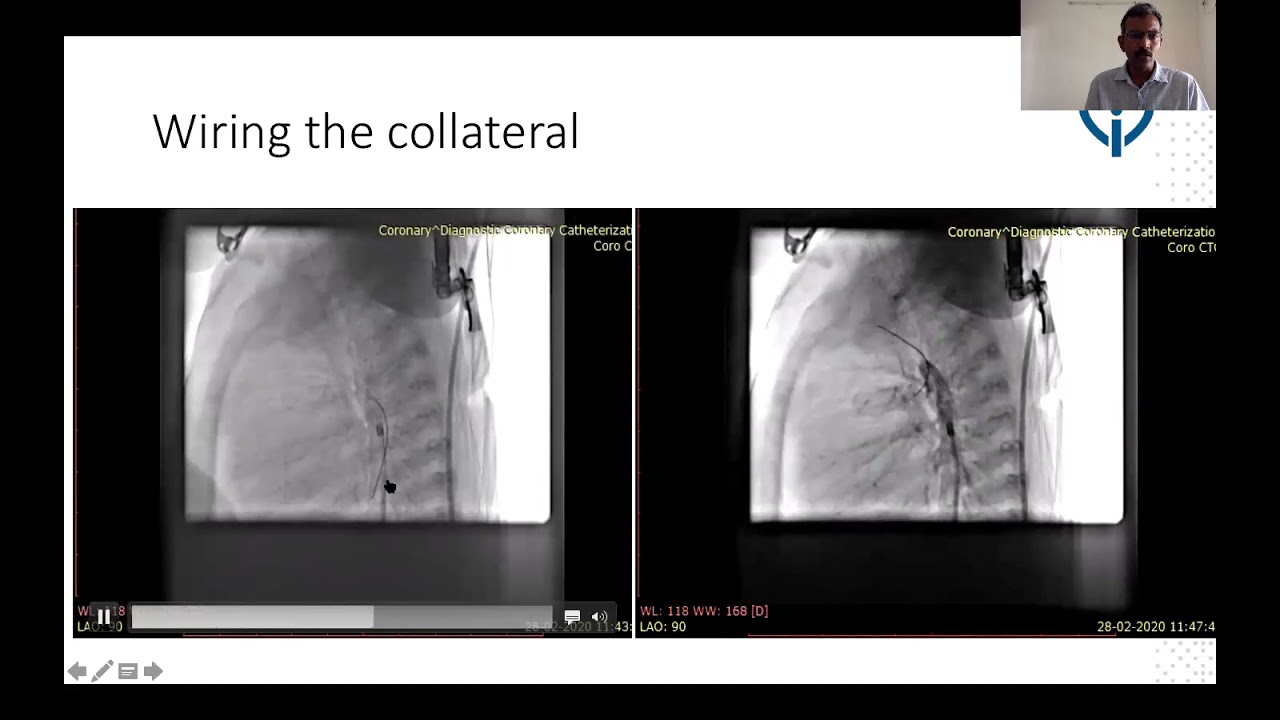

Percutaneous intervention for Coarctation of aorta and rupture of sinus of valsalva in a young woman presenting as heart failure

By: Sanjeev Hanumantacharya Naganur, Chandigarh, India